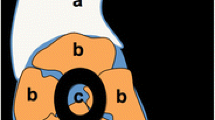

Using this reference system, four possible main morphological variants were identified (Fig. 5): 1. flat shape; 2. convex shape; 3. spiculated shape; and 4. mixed morphology. A detailed description of the 4 morphological variants is shown in Table 3.

The four main morphological variants were identified as follows: 95 cases (31%) with convex shape(Fig. 6A), 127 cases (41%) with flat shape (Fig. 6B), 77 cases (25%) with spiculated shape (Fig. 6C), and 12 cases (4%) with mixed morphology (Fig. 6D).